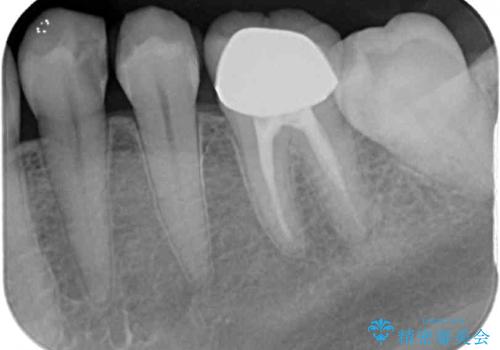

- 冷たいものがしみるとのことで来院された患者様です。

診査を行った結果、第一小臼歯にある樹脂の詰め物(コンポジットレジン)と歯の境目が痛みの原因であることが分かりました。

また、隣接する第二小臼歯も虫歯になっていることも分かったため、2歯を同時に治療するにしました。

下顎の目立つ位置であるため、セラミックインレーによる修復治療を行うこととしました。

精密に型取りを行ったセラミックインレーを装着したことで、治療後にはしみたり痛んだりという症状は治まりました。